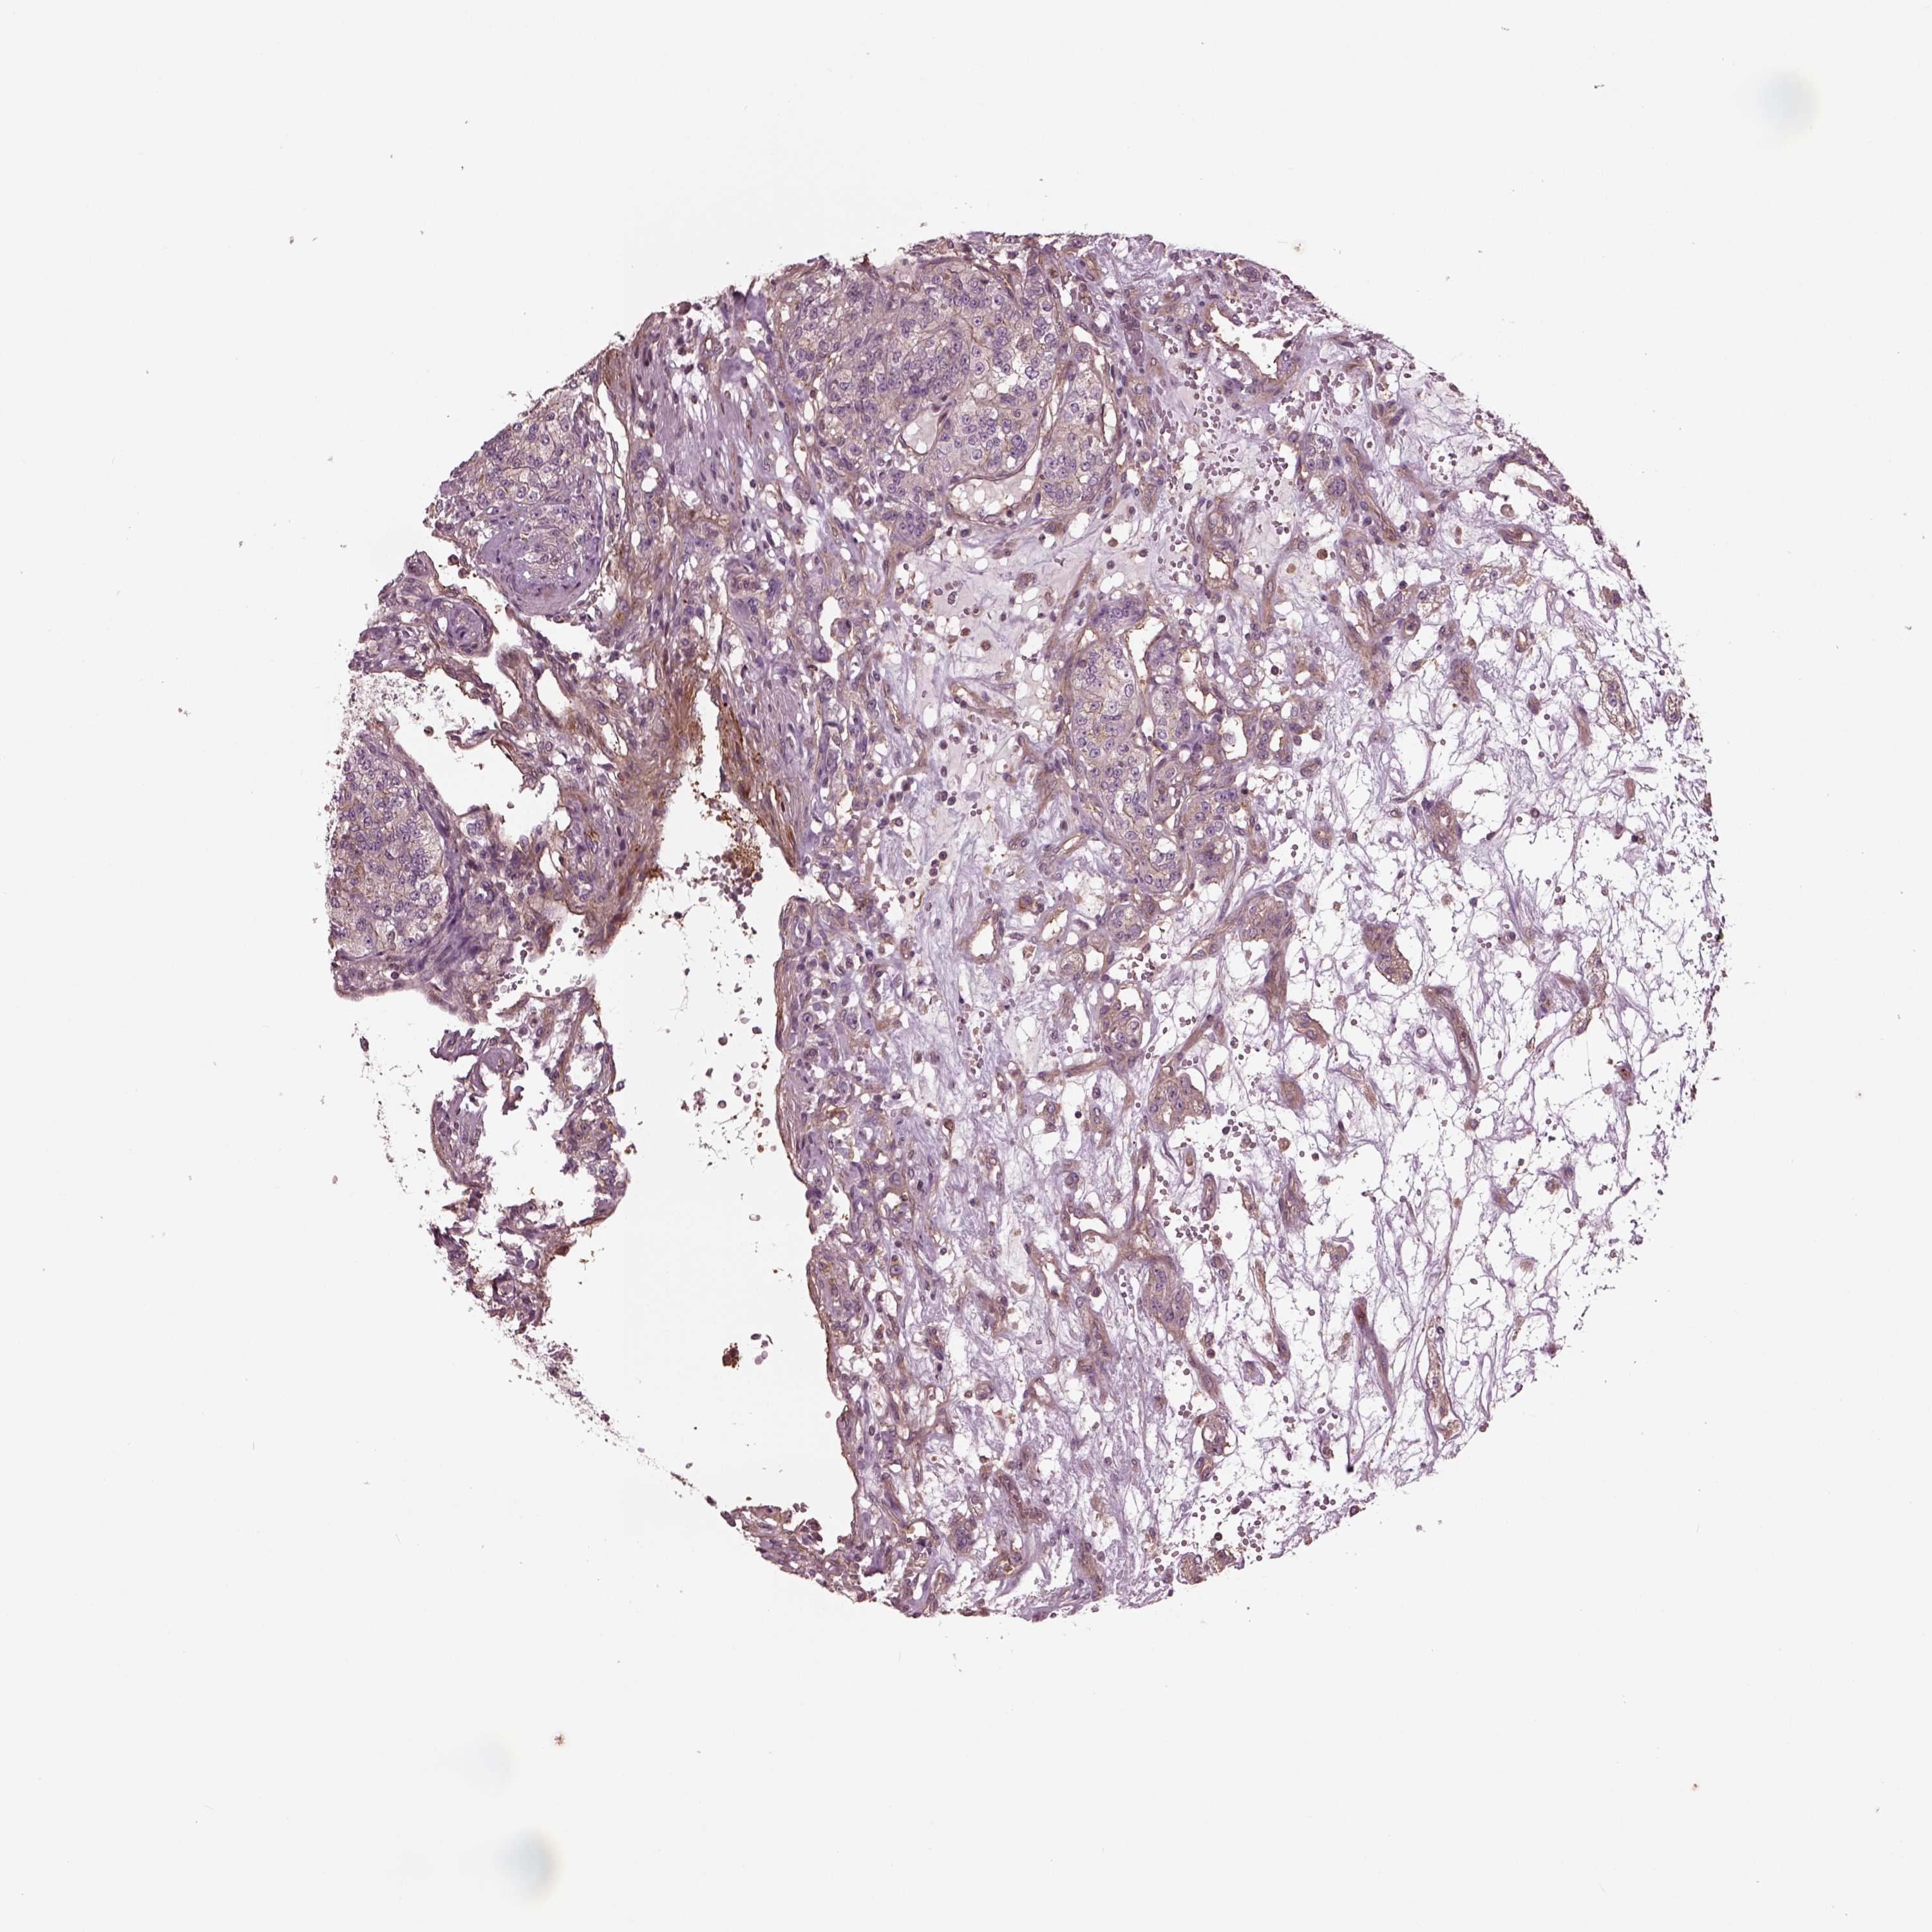

KIDNEY RENAL PAPILLARY CELL CARCINOMA (TCGA) - Interactive survival scatter ploti

The Survival Scatter plot shows the clinical status (i.e. dead or alive) for all individuals in the patient cohort, based on the same data that underlies the corresponding Kaplan-Meier plots. Patients that are alive at last time for follow-up are shown in blue and patients who have died during the study are shown in red.

The x-axis shows the expression levels (FPKM) of the investigated gene in the tumor tissue at the time of diagnosis. The y-axis shows the follow-up time after diagnosis (years). Both axes are complimented with kernel density curves demonstrating the data density over the axes. The top density plot shows the expression levels (FPKM) distribution among dead (red) and alive patients (blue). The right density plot shows the data density of the survived years of dead patients with high and low expression levels respectively, stratified using the cutoff indicated by the vertical dashed line through the Survival Scatter plot. This cutoff is automatically defined based on the FPKM cutoff that minimizes the p-score. The cutoff can be changed by dragging the vertical line or by entering a cutoff value in the square labeled "Current cut-off".

Under the Survival Scatter plot the p-score landscape (black curve; left axis) is shown together with dead median separation (red curve; right axis). Dead median separation is the difference in median mRNA expression between patients who have died with high and low expression, respectively. It is calculated as follows: median FPKM expression of dead patients with high expression - median FPKM expression of dead patients with low expression. This is intended to aid the user in visually exploring custom cutoffs and the associated p-scores and dead median separation.

Individual patient data is displayed and can be filtered by clicking on one or more of the category buttons on the top of the page. Categories describing expression level and patient information include: high, low, alive, dead, female, male and tumor stages. The scale of the x-axis can be toggled between linear and log-scale by clicking on the "x log" button. Mouse-over function shows TCGA ID, patient information and mRNA expression (FPKM) for each patient.

& Survival analysisi